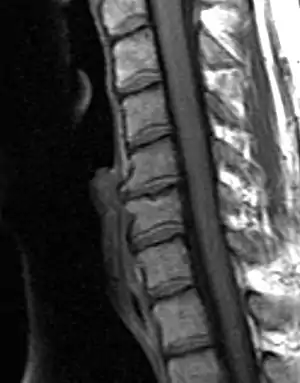

Degenerative changes observed on the intervertebral joints are not considered osteoarthritis (OA) strictly speaking, since OA only affects synovial joints, whereas intervertebral joints are amphiarthrodial, i.e. cartilaginous joints that allow for mild or minimal movement of the articulating elements.[14] Nonetheless, osteoarthritis and spinal arthritis have a very similar manifestation and they are often grouped together in the bioarchaeological literature. Bioarchaeological and clinical studies have demonstrated that the manifestation of spinal arthritis is linked to factors such as age, sex, body size, mechanical stress, bipedal posture, and others.[15] As with OA, spinal arthritis has been traditionally used in bioarchaeological studies to explore different aspects of social and cultural parameters.

Lesley Gregoricka and Jaime Ullinger from the Ohio State University examined the changes in spinal degenerative disease frequencies of the cervical vertebrae from the Early Bronze Age (3150 – 2300 c. BCE) skeletal assemblage of Bab edh-Dhra’ in Jordan. The aim of the study was to confirm or refute whether an increase in sedentism at the site led to declining workloads. Analysis revealed that the frequency of spinal arthritis decreased from 21% to 13% across the Early Bronze Age at the site. This decrease over time was attributed to a reduction in physical stress on the neck resulting from changes associated with carrying loads on the head. Both authors go on to suggest that the semi-sedentary group of the EB IA (3150 – 3050 c. BCE) were probably practicing small-scale horticulture, yet leaving no significant archaeological remains behind; while the later sedentary group of the Early Bronze Age II-III (2900 – 2300 BCE) at Bab edh-Dhra’ lived year-round next to agricultural fields and streams, therefore, travelling shorter distances for transporting crops and water.[16]